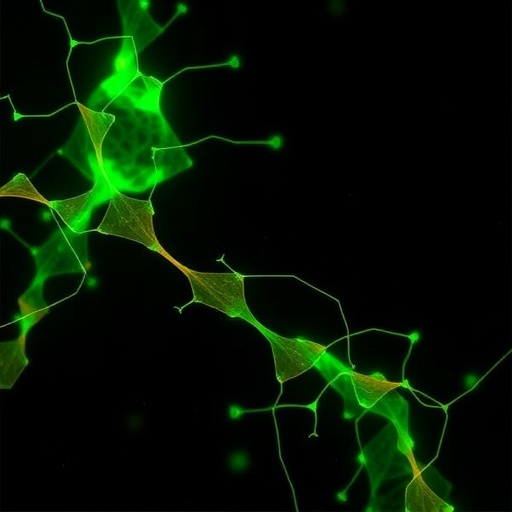

The focus on L1 cell adhesion molecule (L1CAM), a critical protein involved in neural development, forms the core of the investigation. L1CAM’s normal function is essential for neuron migration, axonal growth, and synapse formation. In the context of elevated bilirubin, abnormal modifications such as altered tyrosine phosphorylation and mislocalization within cellular lipid rafts—specialized microdomains within the cell membrane—compromise L1CAM function, which likely contributes to neuronal injury and developmental deficits. This study meticulously examined these molecular alterations and demonstrated that choline supplementation effectively counteracts these deleterious changes, restoring both tyrosine phosphorylation patterns and the proper distribution of L1CAM within lipid rafts in an in vivo model.

Tyrosine phosphorylation is a key post-translational modification that governs protein activity and intracellular signaling. Bilirubin disrupts this finely tuned process on L1CAM, provoking a cascade of cellular dysfunction. The researchers employed sophisticated biochemical and imaging techniques to reveal how bilirubin exposure leads to aberrant tyrosine phosphorylation, thus impairing L1CAM’s interaction with other critical signaling partners. Intriguingly, choline appeared to stabilize these phosphorylation states, suggesting that it may reinforce cellular signaling fidelity under toxic stress conditions. These findings highlight choline’s potential as not merely a nutritional supplement but a biochemical modulator of neuronal resilience.

Another significant aspect illuminated by this research involves lipid rafts—dynamic nano-domains within cell membranes that orchestrate signal transduction by clustering key proteins. Disruption of lipid raft composition or protein localization within these rafts can severely impair cell signaling. Bilirubin-induced redistribution of L1CAM away from lipid rafts impedes its normal signaling pathways, contributing to neuropathology. This study documented that choline administration maintains the integrity of lipid rafts and preserves L1CAM positioning, thereby reinforcing essential neurodevelopmental signaling mechanisms in the face of bilirubin toxicity. This novel mechanistic insight has far-reaching implications for our understanding of membrane biology in neurotoxic conditions.

The neuroprotective properties of choline emerging from this study add a fascinating layer to its already established role in brain development. As a precursor for acetylcholine—a critical neurotransmitter—and a structural component of phospholipids in cell membranes, choline’s ability to preserve protein functionality within lipid rafts unveils an additional dimension to its biological significance. This research fosters a paradigm shift in how we interpret choline’s actions, prompting future inquiries into its modulatory capacity over post-translational modifications and membrane microdomain dynamics under pathological stress.

Delving into the broader mechanistic landscape, this research enriches our understanding of how the intersection of lipid biochemistry and protein phosphorylation governs neurodevelopment under stress. Lipid rafts, often overlooked as mere structural domains, are now emerging as critical hubs of cellular communication, susceptible to environmental insults such as bilirubin. Choline’s role in stabilizing these microenvironments underscores the delicate balance between nutritional status, membrane organization, and protein signaling that sustains brain health.